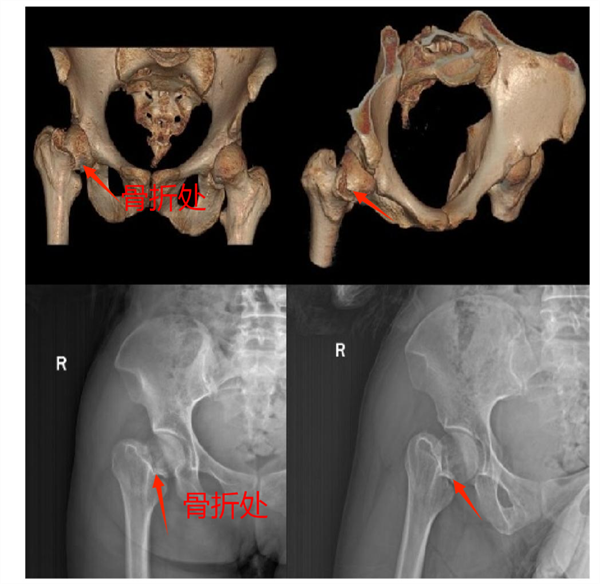

患者王某因右股骨颈骨折(头下型)入院,术前X片和三维CT精准检查,为手术方案提供依据。股骨颈骨折,尤其是头下型骨折治疗难度大。此次采用的股骨颈动力交叉钉系统(FNS)是保髋内固定新技术,优势显著。在C臂透视和骨科牵引床辅助下,医生通过小切口就完成闭合复位和内植物置入,实现骨折端有效固定。相比传统空心螺钉固定,FNS可滑动加压促进骨折愈合,提供成角稳定性,抗内翻并保证支撑强度,防退钉和股骨头切出,患者也能早期不负重功能锻炼,减少并发症。

术前X片以及术前三维CT